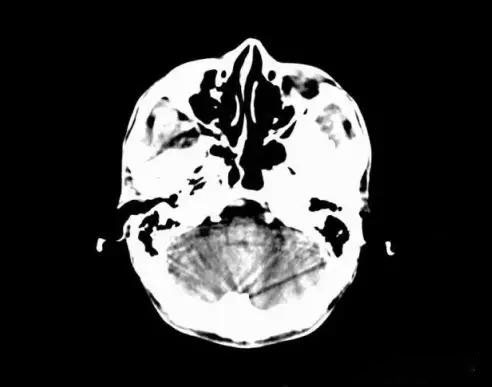

5、部分容積效應(yīng)產(chǎn)生的偽影及對策

部分容積效應(yīng)偽影的形狀可因物體的不同而不一樣,一般在重建后橫斷面圖像上可見條形、環(huán)形或大片干擾的偽像。最常見和典型的現(xiàn)象是在頭顱橫斷面時的顳部出現(xiàn)的條狀偽影,又稱哼氏偽影。該偽影現(xiàn)象可采用薄層掃描而減弱;在西門子系列的CT機(jī)中.用VAR掃描技術(shù)可抑制該偽影。

6、周圍間隙現(xiàn)象偽影及對策

在同一掃描層面內(nèi),與層面垂直的兩種相鄰且密度不同的組織,其邊緣部的CT值不能準(zhǔn)確測得,因而在CT圖像上,其交接處圖像不能清楚分辨,這種現(xiàn)象即為周圍間隙現(xiàn)象,此種現(xiàn)象的實質(zhì)仍是一種部分容積效應(yīng)。通過減薄掃描層厚,可減少此類偽影的發(fā)生。